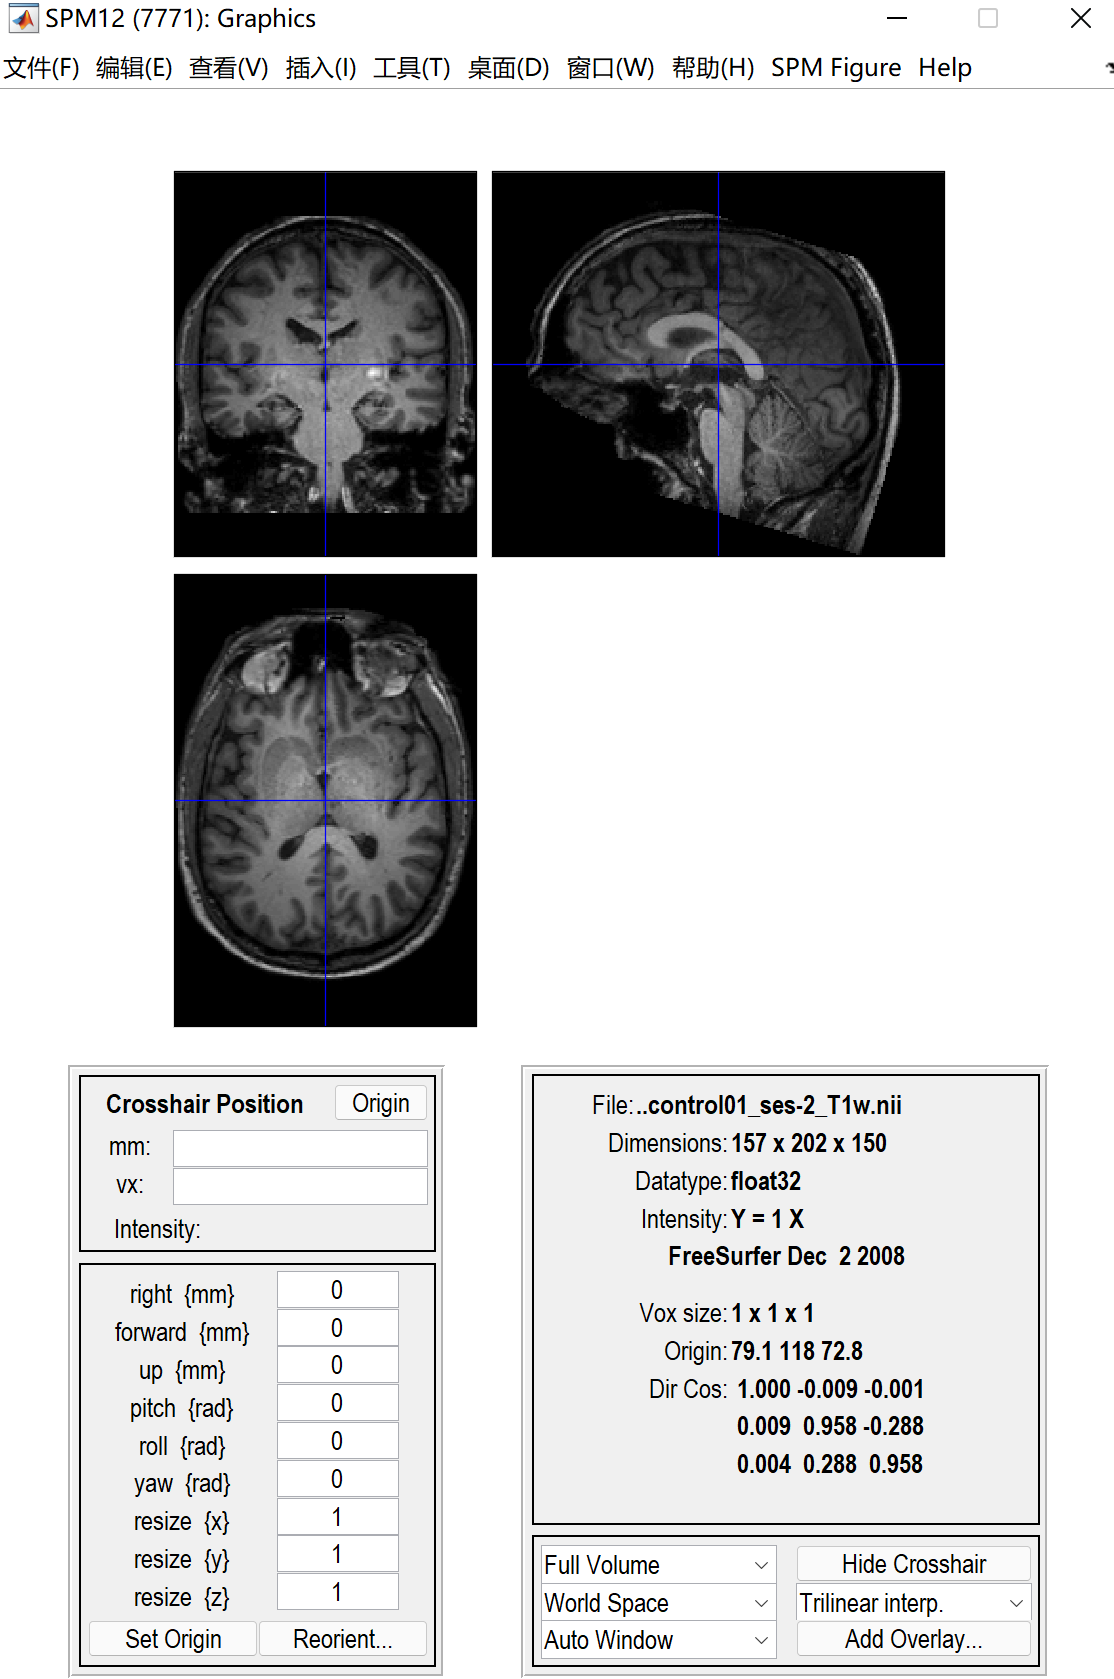

一个这样的页面,我们可以看到一个蓝色的十字线,这个线的交叉点就是我们要调整的地方,手动将交叉点放在大概下图这个位置(就是前联合的位置),前联合的位置怎么确定可以去查一下,网上有很多教程。我的理解就是大概在下图这个红色的圆里。点一下set origin之后就会出现坐标位置。然后一定要点击一下Reorient,才算是调整成功了。在这里插入图片描述在这里插入图片描述